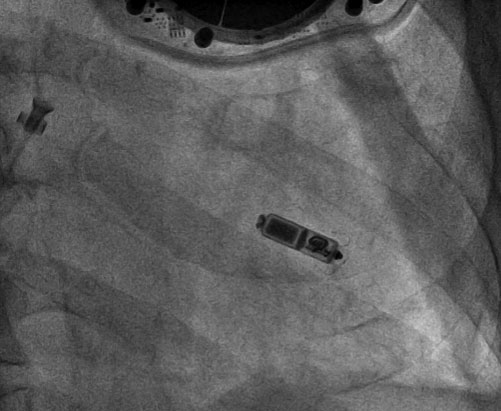

在移除感染装置后,新的起搏器植入时机和部位也是临床上不得不面临的重要问题。为避免再次感染风险,权衡利弊后,电生理团队为陈爷爷制订了心腔内植入无导线起搏器的策略。无导线起搏器作为心脏起搏领域的一次飞跃性创新,无需植入起搏电极导线,也无需在胸部皮下制作囊袋放置脉冲发生器,因此避免了起搏器囊袋破溃或起搏导线磨损断裂引起的感染。在移除旧的起搏装置一周后,薛玉梅主任和廖洪涛主任一道经股静脉入路为陈爷爷植入了Micra无导线起搏器,整个手术仅用时半小时。术后陈爷爷恢复良好。

Micra无导线起搏器放置在右室心尖部